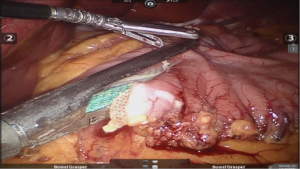

Operative room set-up (Figure 4 )

Patient cart brought in from head end. The central column of the patient cart, target anatomy (stomach in this case) and the camera port, all lie in single straight line. Two mobile video monitors are placed on either side of the patient to enable the assistants to easily watch and help at every step of procedure, to provide ergonomic comfort.